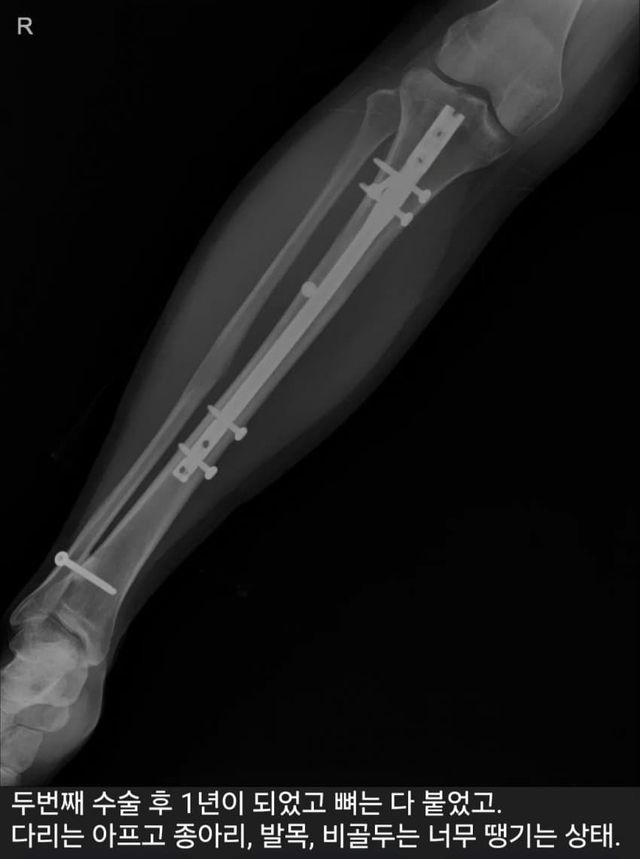

1. 6cm 늘림

2. 다리 아픔

3. 3.5cm 줄임